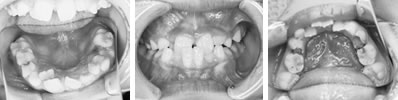

治療開始時年齢は6歳半でしたが、永久歯は1本もありませんでした。右上の乳歯Dから左上の乳歯Cまでが反対咬合の状況でした。

レントゲンの検査、家族暦などから骨格的な下顎前突の程度が大きいことがわかりましたので、オトガイ帽装置(チンキャップ)を使用することになりました。

普段のかみ合わせのまま下顎を後ろに押し下げようと力をかけた場合、上顎前歯と下顎前歯がぶつかって上顎まで後ろに下げようとする力が働いてしまいます。そこで、チンキャップを使用する場合には前歯の干渉を避けるためにクリアプレートを併用しました。

1年後(7歳半)の口腔内 下顎前歯が抜け替わりましたが、反対咬合の状態です。

装置使用開始4ヶ月目には反対咬合が解消されています。